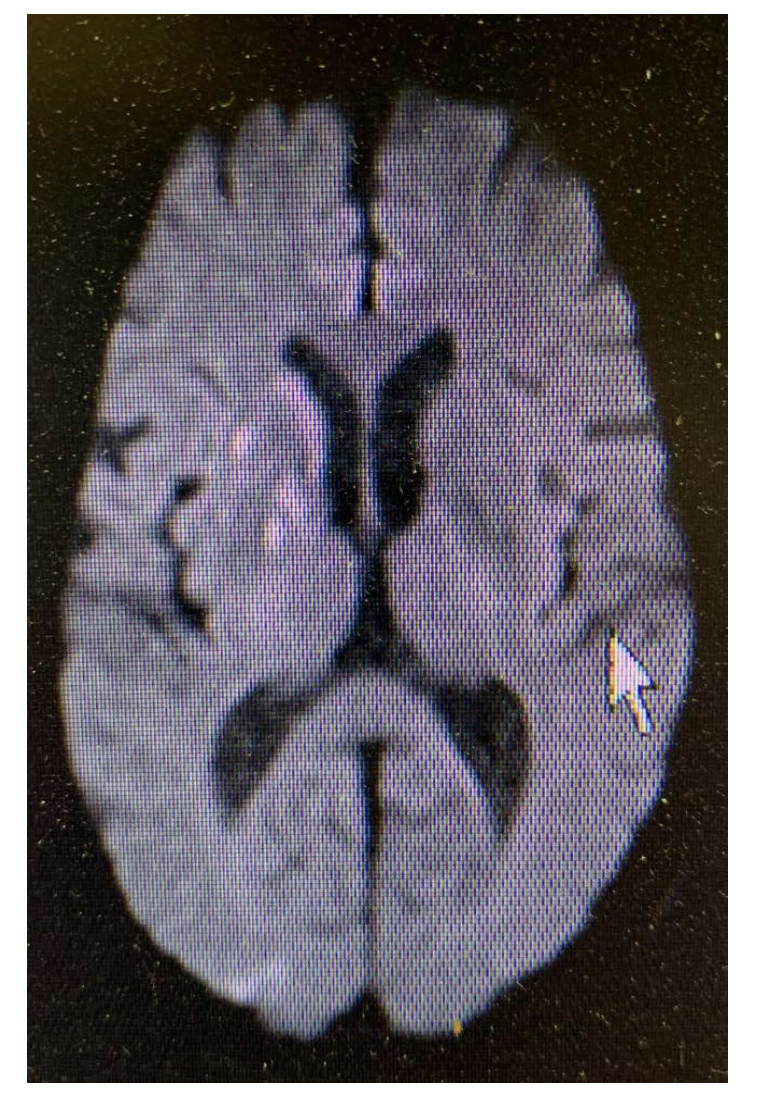

He had mild left face, arm, and leg weakness. Magnetic resonance imaging (MRI) confirmed multiple small areas of acute ischemia in the right frontal and parietal lobes (Figure 2). MR angiography showed a right internal carotid artery stenosis. He was treated with aspirin, argatroban, and edaravone.